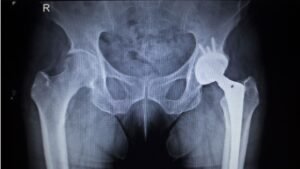

2. X-ray

The most important test for hip osteoarthritis. It shows:

- Narrowed joint space

- Bone spurs (osteophytes)

- Bone hardening beneath cartilage (sclerosis)

Hip Replacement (Total Hip Arthroplasty)

The damaged ball and socket are replaced with artificial components that restore smooth movement.